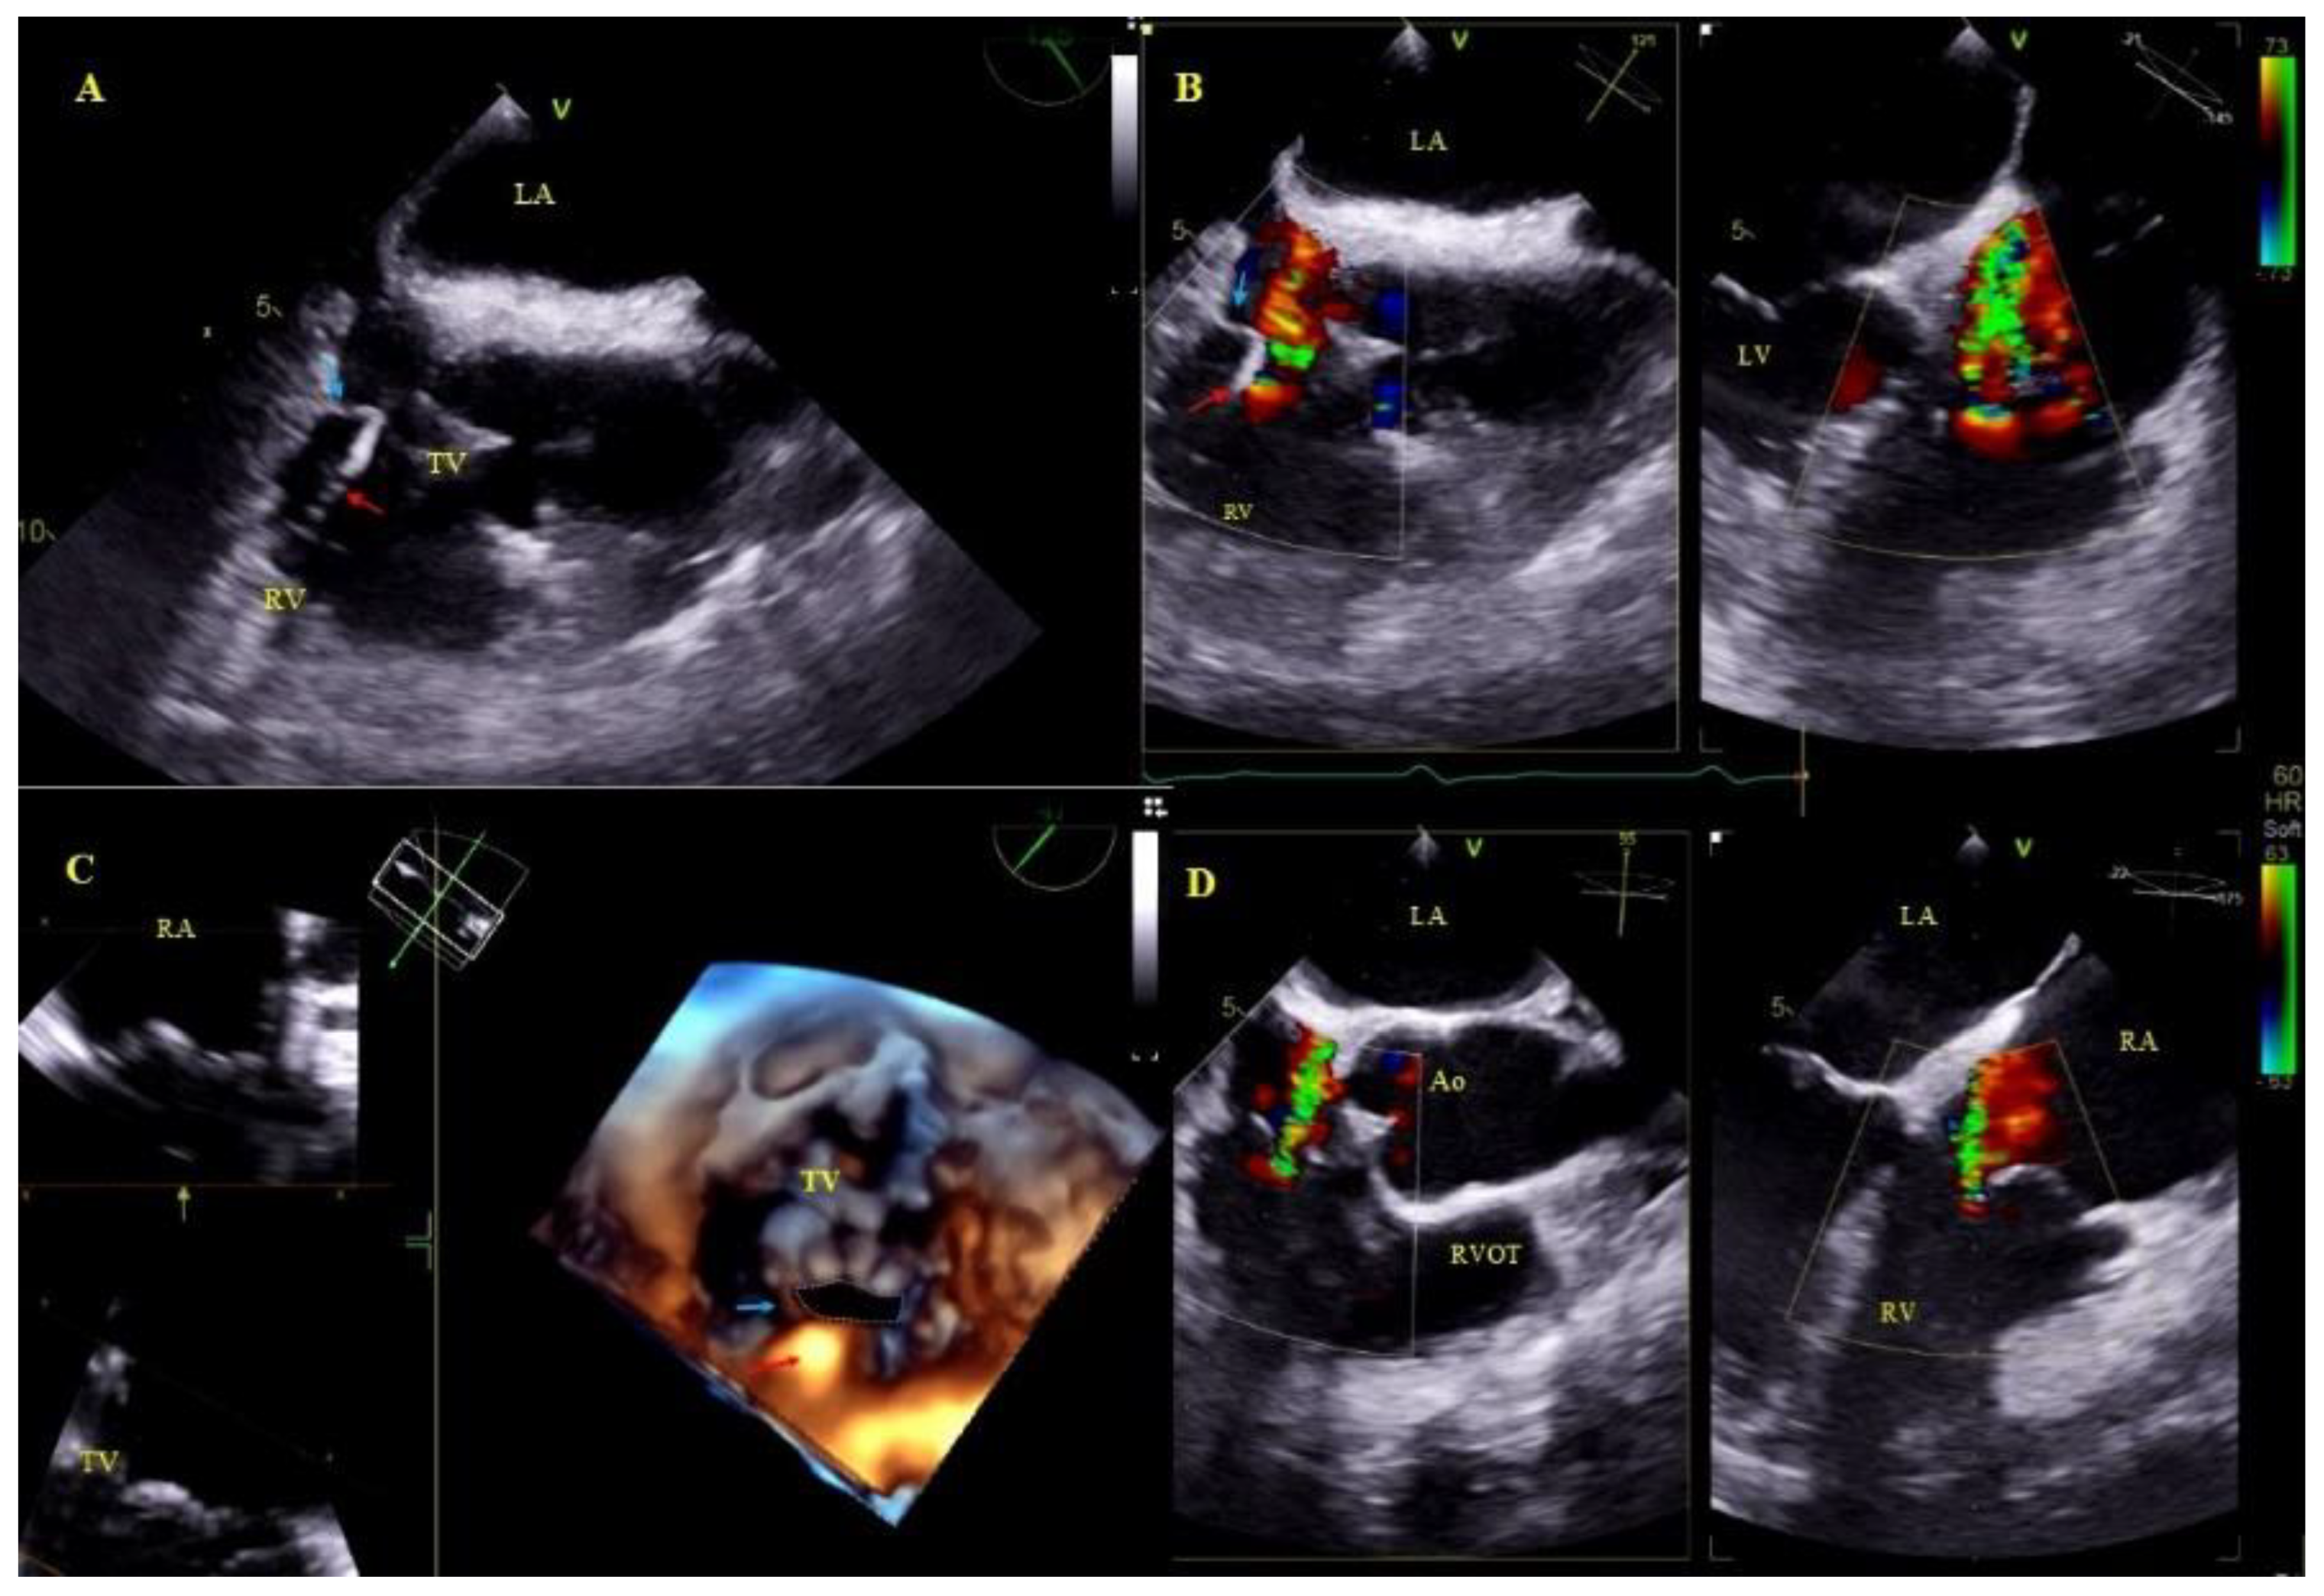

2.5. Echocardiographic Findings Associated with Endocardial Leads: Definition and Classification According to the Anatomy and Characteristic Features

- Lead-dependent tricuspid dysfunction was not significantly associated with the length of survival. This can be attributed to the fact that most patients with LDTD were referred for the intervention because of the lead propping one of the leaflets open, which was corrected to varying extent during TLE.

- Excessive lead loops (loop in the right atrium, loop crossing the TV, loop in the right ventricle or pulmonary artery) in univariate and multivariate Cox analysis were significantly associated with better survival odds. The reason was that this abnormality was the indication (main or accompanying) for lead replacement and no patient left our facility with abandoned leads.